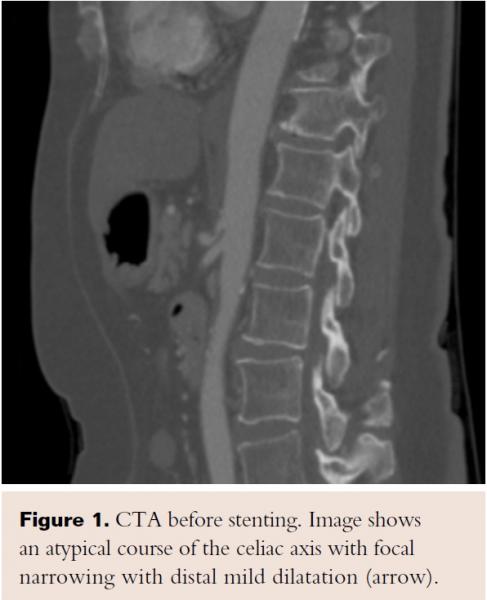

Immediately after the procedure, the patient’s abdominal pain resolved, and her appetite returned the following day. After 1 month, she started having some epigastric abdominal pain related to food. A repeat CT angiogram showed complete patency of her stent (Figure 8). An abdominal ultrasound showed a cholelithiasis and gall bladder polyp. At 6-month follow-up, the patient had regained 13 lb and had no problems with eating her regular meals. The patient was followed for the next 4 years, and remained asymptomatic for the entire time.